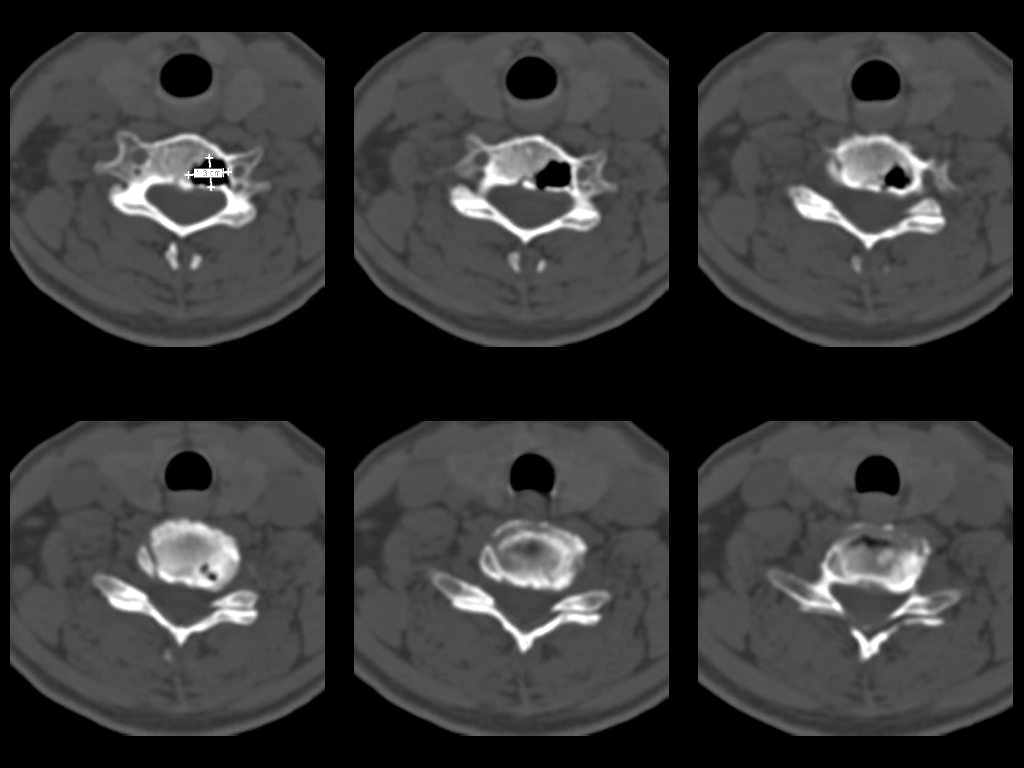

У женщины 49 лет, при рентгенографии шейного отдела в теле С6 выявлен участок деструкции.Часть N1 Больная находилась в неврологическом отделении с диагнозом энцефалопатия. Была проведена КТ тела С6, 26.12.2002 выявлен участок деструкции 0,9х1,2 см, плотность участка составляет -1022 ед.Н. аналогичная плотности воздуха в трахее.Возникает вопрос что это? Метастаз, киста,или какой то вредный анаэроб грызет тело позвонка?Через пол года 03.06.2003 произведено повторное исследование. Отмечается отрицательная динамика. Участок деструкции увеличился в размерах, увеличелась площадь разрушения задней поверхности тела С6.

Первые 2 серии снимков это от 2002г, вторые 2 серии от 2003 г. Относительно размеров, сообщю дополнительно все перермерю на томографе.

за 2003 1,3х0,9х1,2 мм. Но контур деструкции стал более неровный и внедрение в дужку С6 увеличелось.

Наличие выраженных дистрофических изменений, а также сообщение полости в теле позвонка С6 с полостью межпозвонкового диска в сегменте С5-С6, а также наличие газа в полости межпозвонкового диска С5-С6 спереди, на границе фиброзного кольца и пульпозного ядра (3-й слева срез в нижнем ряду на второй из представленных КТ) делает диагноз остеохондроза, осложненного вакуум-феноменом и прорывом газа в полость тела позвонка с формированием воздушной кисты (пневмкисты) несомненным.